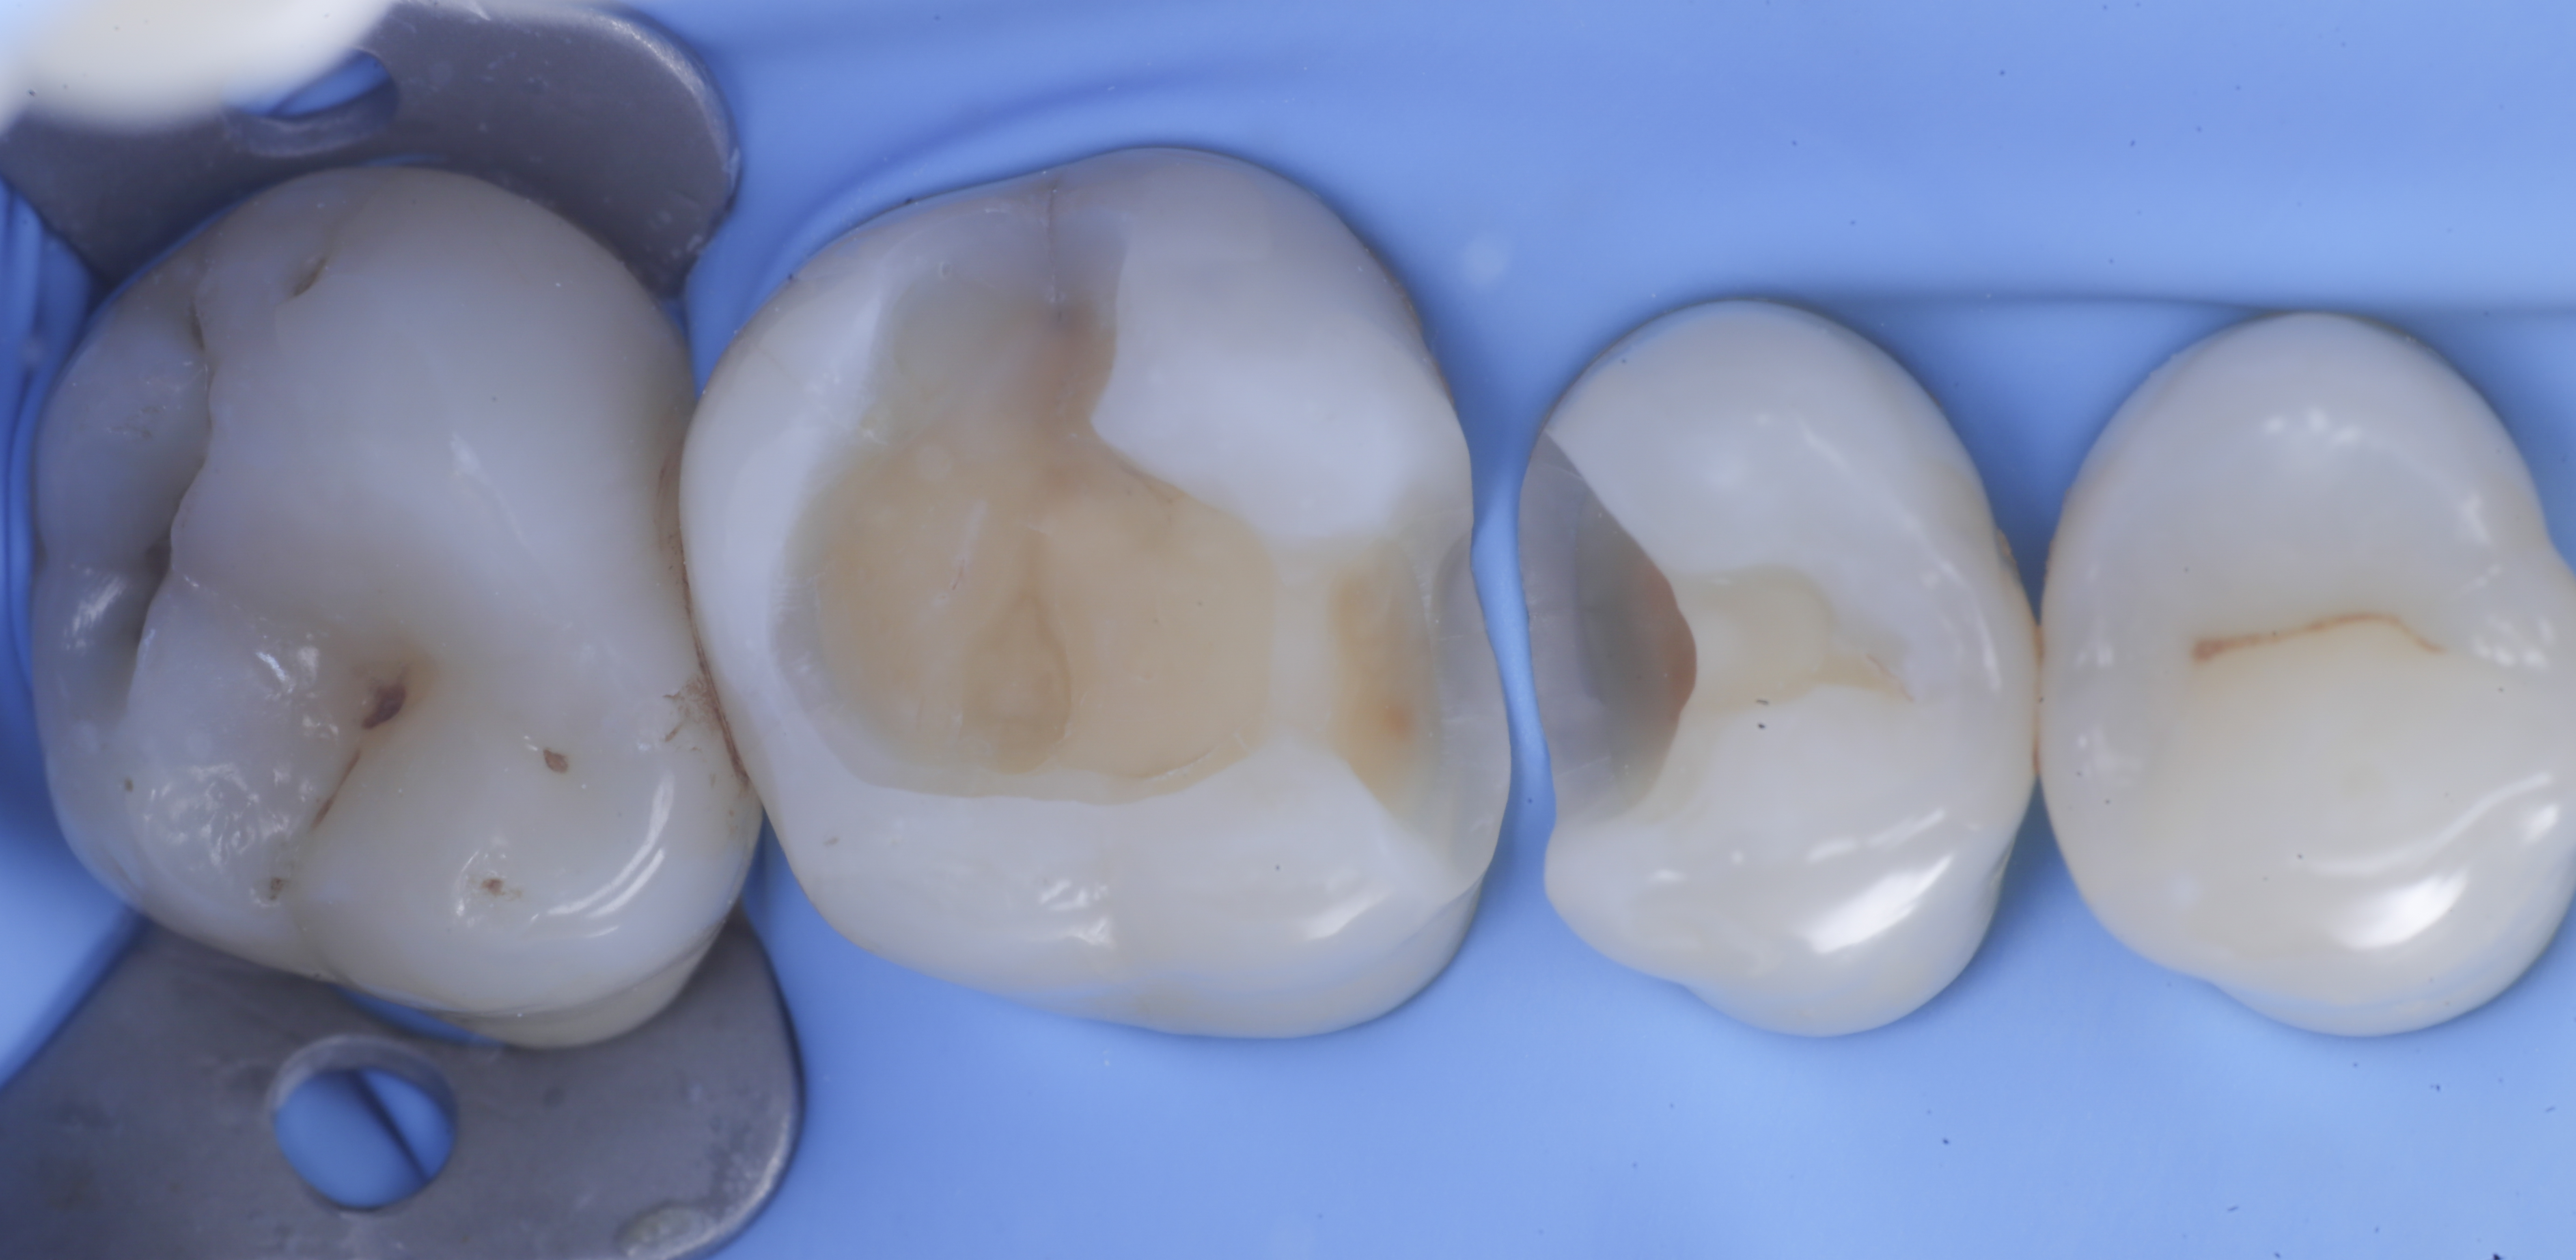

Una volta eliminato completamente il composito, si procede con la detersione della dentina con frese multilama ed alla rifinitura dei margini di smalto che dovranno essere robusti e puliti.

foto 2 Isolamento e aspetto delle cavità ultimate

foto 3 Aspetto vestibolare della cavità ultimate